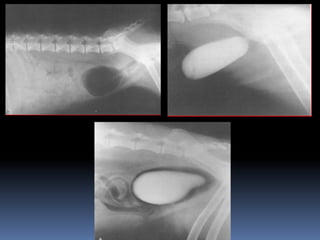

Doc, Me tragué una pelota

Doc, Me traguéuna pelota